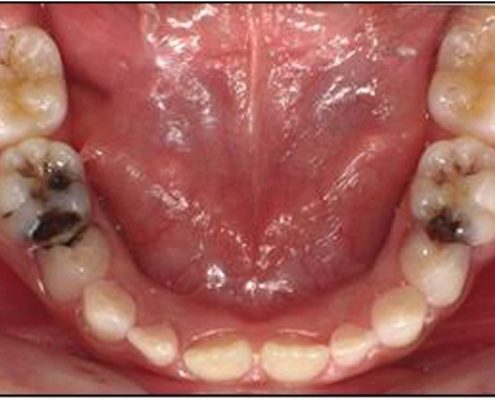

چرا دندان ها سیاه می شوند؟